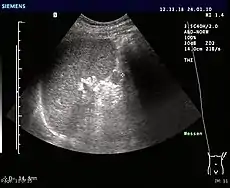

- Ultrasonography of an accessory spleen.

An accessory spleen is a small nodule of splenic tissue found apart from the main body of the spleen. Accessory spleens are found in approximately 10 percent of the population[1] and are typically around 1 centimetre in diameter. They may resemble a lymph node or a small spleen. They form either by the result of developmental anomalies or trauma.[2] They are medically significant in that they may result in interpretation errors in diagnostic imaging[2] or continued symptoms after therapeutic splenectomy.[1] Polysplenia is the presence of multiple accessory spleens rather than one normal spleen.

If splenectomy is performed for conditions in which blood cells are sequestered in the spleen, failure to remove accessory spleens may result in the failure of the condition to resolve.[1] During medical imaging, accessory spleens may be confused for enlarged lymph nodes or neoplastic growth in the tail of the pancreas,[5] gastrointestinal tract, adrenal glands or gonads.[2]